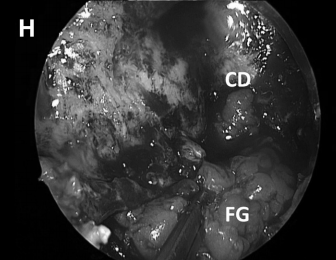

▼然后肿瘤被切除。在图8G中,可见肿瘤基底部暴露,并且颈静脉孔神经部组织可以通过组织质地来区分。

▼首先应用一层TachoSil脂肪移植物覆盖(图8H)

▼然后使用中鼻甲粘膜进行(图8I)进行闭合。

CD,斜坡凹陷;S,蝶鞍;SR,蝶嘴;T,肿瘤。